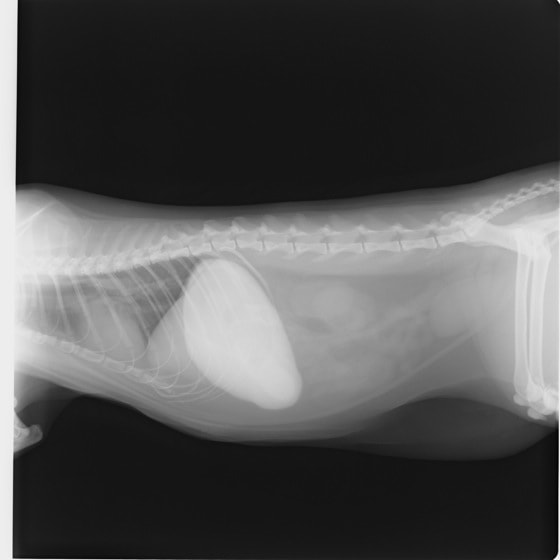

4歳 アメリカンショートヘアー

主訴:3日前から嘔吐が続き、食欲も落ちてきたのこと。

対症療法(症状に対する治療)に反応しないため、精査を実施。

一般血液検査:問題なし

単純レントゲン検査:胃内ガス陰影・腸内ガスが少量認められる。

嘔吐が改善しないため、消化管バリウム造影検査を実施。

消化管バリウム造影レントゲン

バリウム造影3時間経過するも、胃内からバリウム排泄なく同日内視鏡検査を実施。